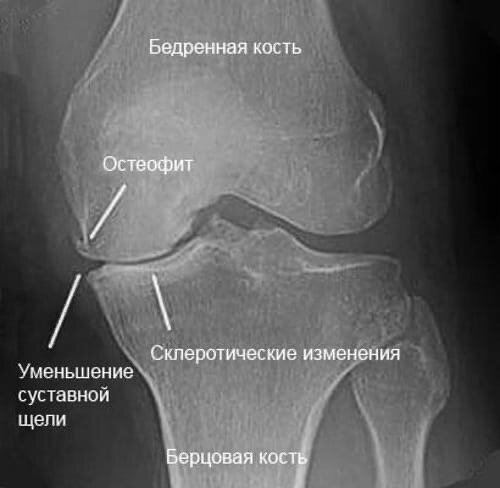

Костная ткань человека - очень прочная и гибкая структура, она способна выдерживать нагрузки в сотни тонн. Но иногда что-то идёт не так… Нарушение обмена кальция, систематические перегрузки, другие деформирующие процессы могут привести к образованию героев сегодняшнего поста. Могут появиться они - остеофиты.

Снова древние греки «помогли» с названием - оно образовано от двух корней, означающих «кость» и «расти». Под действием различных повреждающих факторов (причиной которых может быть абсолютно всё - от наследственности до сломанной спинки вашего любимого кресла) костная ткань начинает патологически увеличиваться в объёме. Следует различать понятия экзостоз и остеофит. Первый - общее название «лишних» костных выростов. Второй - тоже разрастание костной ткани, но преимущественно в области суставных поверхностей кости. Так, на рентгенограммах неправильно треугольные острые выступы на суставах кистей, головке бедренной кости или телах позвонков - остеофиты. А всем известная «пяточная шпора» - строго говоря, экзостоз.

Как я уже говорил, причины развития остеофитов многочисленны. Часто они всего лишь сопровождают естественные процессы старения организма. Но так же могут быть следствием разных заболеваний - нарушение обмена, остеомиелит, диабет и пр.

Если мы говорим о позвоночнике, то остеофиты краев тел позвонков, развивающиеся, например, из-за дегенеративных процессов, могут образовывать обширные наросты, сдавливающие межпозвонковые отверстия и проходящие там нервные корешки спинного мозга. Как раз в таких случаях пациент обычно говорит: «Ох уж, этот радикулит!..». На самом деле, остеофиты могут даже заблокировать сустав! Это происходит, когда они растут как сталактит и сталагмит в пещере, сливаясь в единое целое и ограничивая подвижность сустава.

Несмотря на вышесказанное, чаще всего пациент даже и не догадывается о наличии у него остеофитов, пока не сделает рентген, КТ или МРТ, так как факт их существования не обязательно сопровождается болевым синдромом. Поэтому в большинстве случаев лечение не требуется, нужен только контроль за их дальнейшим развитием.